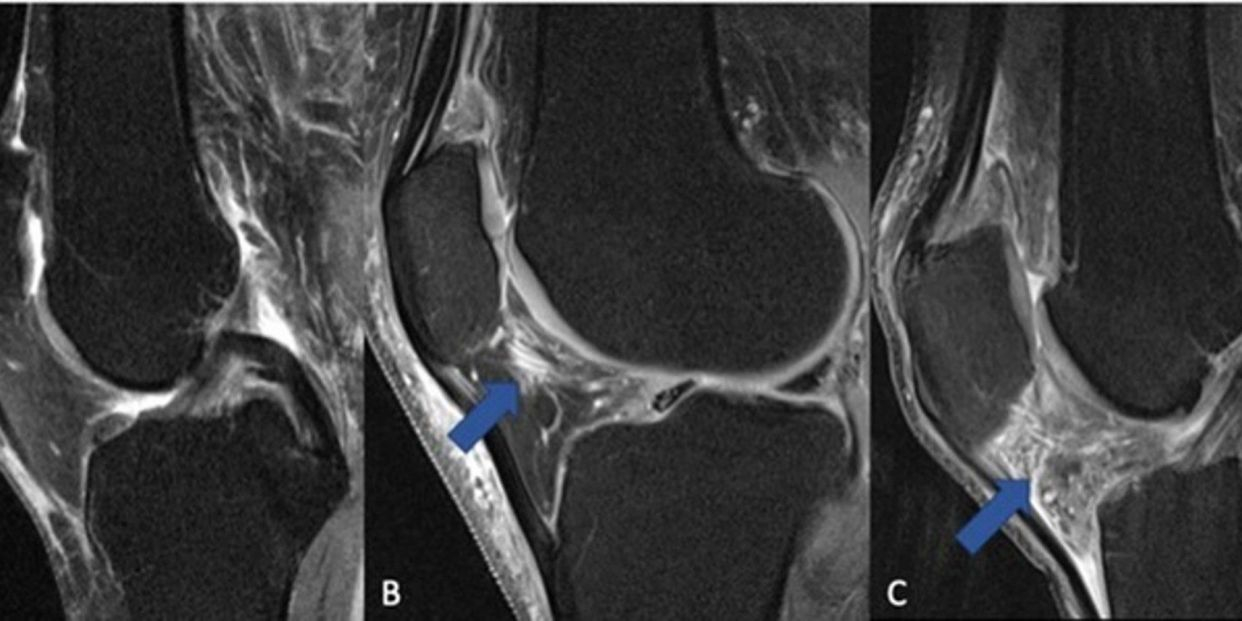

"Hasta la fecha, no se ha aprobado ninguna terapia curativa para curar o reducir la progresión de la artrosis de rodilla. Los AINE se utilizan con frecuencia para tratar el dolor, pero sigue siendo un debate abierto el modo en que el uso de AINE influye en los resultados de los pacientes con artrosis. En particular, el impacto de los AINE en la sinovitis, o la inflamación de la membrana que recubre la articulación, nunca se ha analizado utilizando biomarcadores estructurales basados en la RM", ha comentado la autora principal del estudio, Johanna Luitjens, becaria postdoctoral del Departamento de Radiología e Imagen Biomédica de la Universidad de California en San Francisco (Estados Unidos).

Los investigadores se propusieron analizar la asociación entre el uso de AINE y la sinovitis en pacientes con artrosis de rodilla y evaluar cómo el tratamiento con AINE afecta a la estructura de la articulación a lo largo del tiempo. "La sinovitis interviene en el desarrollo y la progresión de la artrosis y puede ser un objetivo terapéutico. Por lo tanto, el objetivo de nuestro estudio era analizar si el tratamiento con AINE influye en el desarrollo o la progresión de la sinovitis e investigar si los biomarcadores de imagen del cartílago, que reflejan los cambios en la artrosis, se ven afectados por el tratamiento con AINE", ha explicado Luitjens.